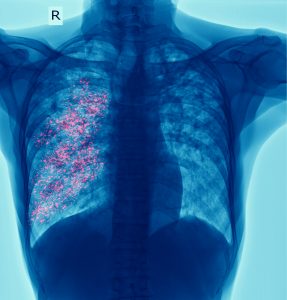

Tuberculosis (TB) is caused by a bacterium (or germ) called Mycobacterium tuberculosis

TB typically affects the lungs but can also impact other parts of the body, such as the brain, kidneys, or spine. TB can also affect multiple parts of the body at the same time. For example, TB can affect both the lungs and lymph nodes.